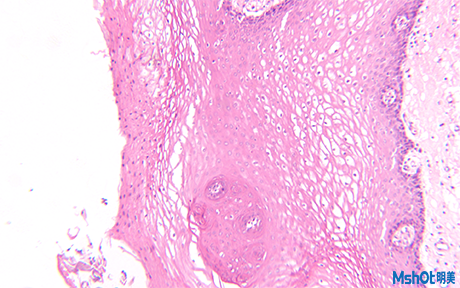

免疫熒光技術(shù)又稱熒光抗體技術(shù),是標(biāo)記免疫技術(shù)中發(fā)展的一種。它是在免疫學(xué)、生物化學(xué)和顯微鏡技術(shù)的基礎(chǔ)上建立起來的一項(xiàng)技術(shù)。北京大學(xué)深圳醫(yī)院口腔科實(shí)驗(yàn)室需要用到熒光顯微鏡搭配顯微鏡相機(jī)來觀察熒光細(xì)胞。

老師需要拍攝活體熒光細(xì)胞,深圳辦事處的工程師給老師推薦明美高性價(jià)比的倒置熒光顯微鏡MF52,這款熒光顯微鏡采用好的無限遠(yuǎn)光學(xué)系統(tǒng),配置長工作距離平場物鏡與大視野目鏡。落射熒光顯微系統(tǒng)采用模塊化設(shè)計(jì)理念,可以快捷地調(diào)整照明系統(tǒng),切換熒光濾色片組件。此款熒光顯微鏡可應(yīng)用于細(xì)胞組織,透明液態(tài)組織的顯微觀察,也可用于生物制藥,醫(yī)學(xué)檢測、疾病預(yù)防等領(lǐng)域內(nèi)的熒光顯微觀察。